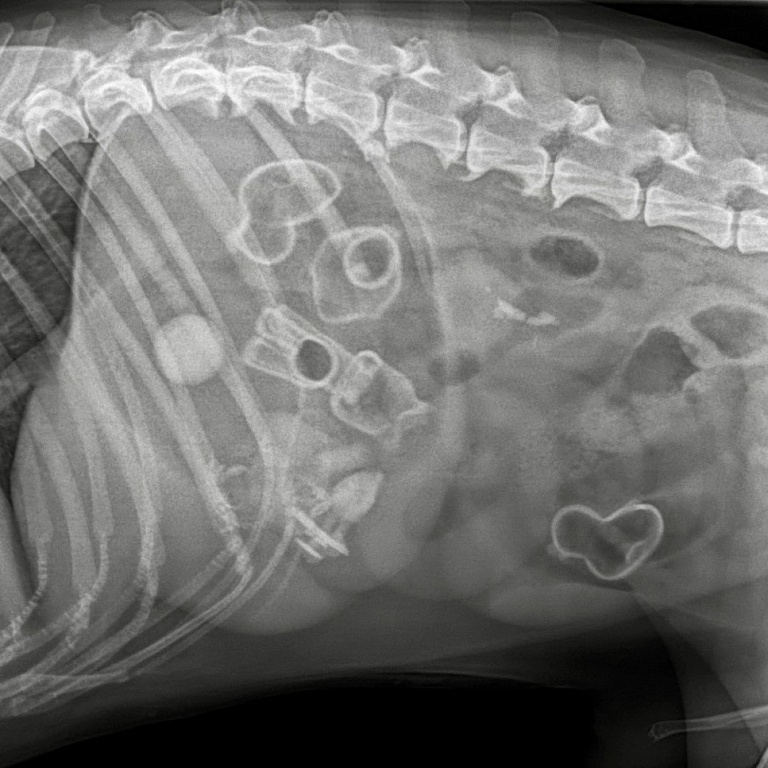

Семилетний пёс – любимец всей семьи, за самочувствием которого следят очень внимательно. Но как-то раз хозяева заметили, что в течение нескольких дней питомец пребывает в вялом и подавленном состоянии, поэтому решили показать его ветеринару. Осмотрев собаку, доктор тут же отправил четвероногого на рентген. На рентгене всех ждал сюрприз – в пищеварительной системе у пациента был обнаружен целый арсенал детских игрушек. Ветеринары экстренно прооперировали пса. Операция прошла успешно, специалистам удалось удалить все инородные тела.

Врачи достали из желудка и кишечника хвостатого пострадавшего лошадку, резиновых уточек и другие детские игрушки. Судя по изъятому содержимому, питомец даже не пытался разгрызть игрушки, а просто глотал их целиком.